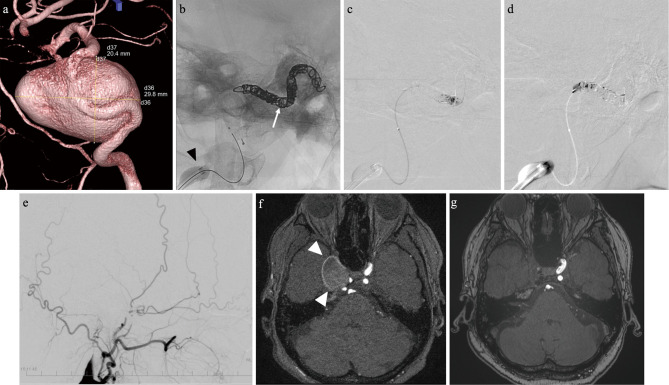

Parent artery occlusion for large or giant internal carotid artery aneurysms remains a necessary procedure in the era of flow diverters. Endovascular parent artery occlusion is currently performed using detachable balloons or coils, which are difficult to obtain or costly. At our institution, we have devised a technique for combining n-butyl-2-cyanoacrylate and coils with flow control to solve this problem. Patients who underwent parent artery occlusion for large or giant internal carotid artery aneurysms with a follow-up period of more than 12 months were included. Imaging outcomes were evaluated for complete or incomplete aneurysmal occlusion and with or without aneurysmal shrinkage. The clinical outcome was based on changes in the modified Rankin Scale. Ten patients (ten aneurysms) were included. Their average age and average follow-up period were 68.4 years and 36 months, respectively. Complete occlusion and favorable clinical outcome were observed in all cases. The parent artery occlusion using a combination of coils and n-butyl-2-cyanoacrylate with flow control technique is effective for both imaging and clinical outcomes.